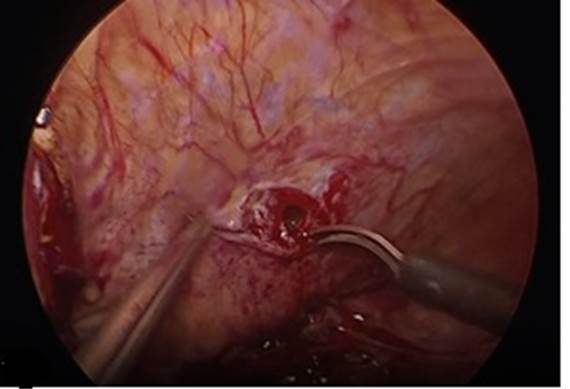

5. Movilización y disección vesical. Se incide vejiga de forma vertical por debajo de la reflexión de globo vesical (Fig. 7) y se localiza el catéter del trayecto fistulosos, así como catéteres ureterales.

6. Reparación de la fístula. Se diseca la pared posterior de la vejiga de la pared anterior de la vagina con disección roma o cortante. Se procede a realizar fistulectomía circunferencial con corte frío (Fig. 8), se completa disección y separación de pared vaginal de la vesical (Fig. 9).